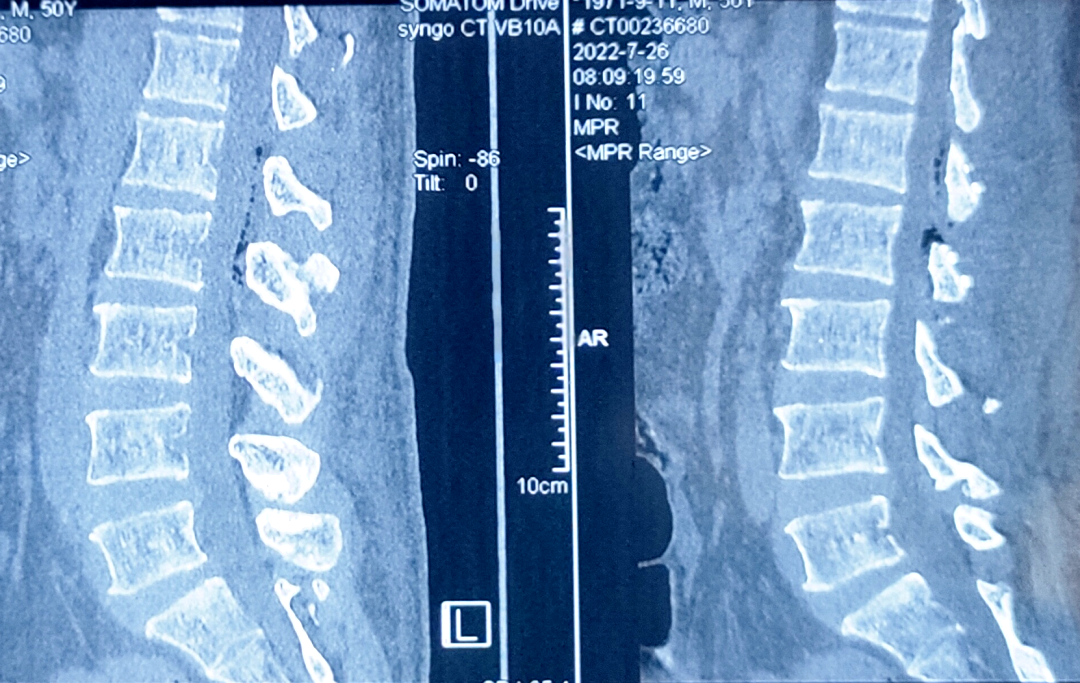

脊髓肿瘤术中

切除前

切除后

脊髓肿瘤术前

脊髓肿瘤术后